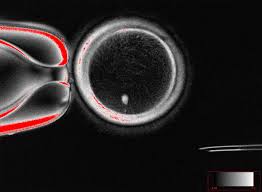

Dari 82 telur fungsional yang dihasilkan, sebagian besar tidak berkembang melewati tahap 4-8 sel karena kelainan kromosom. Hanya sekitar 9% yang mencapai tahap blastokista pada hari ke-6, tahap yang biasanya dipindahkan untuk memulai kehamilan.